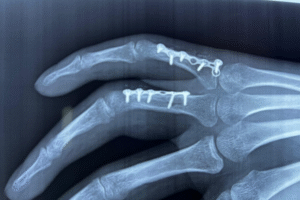

El dedo en gatillo es un padecimiento común en el ámbito laboral por actividades repetidas que suelen lesionar al aparato flexor y por consecuente generar dolor al realizar el movimiento. El tratamiento con medicamentos y desinflamatorios puede ayudar a controlar los síntoma. Cuando el dolor es persistente y el bloqueo o engatillamiento del dedo evidente el tratamiento quirúrgico es el tratamiento de elección.